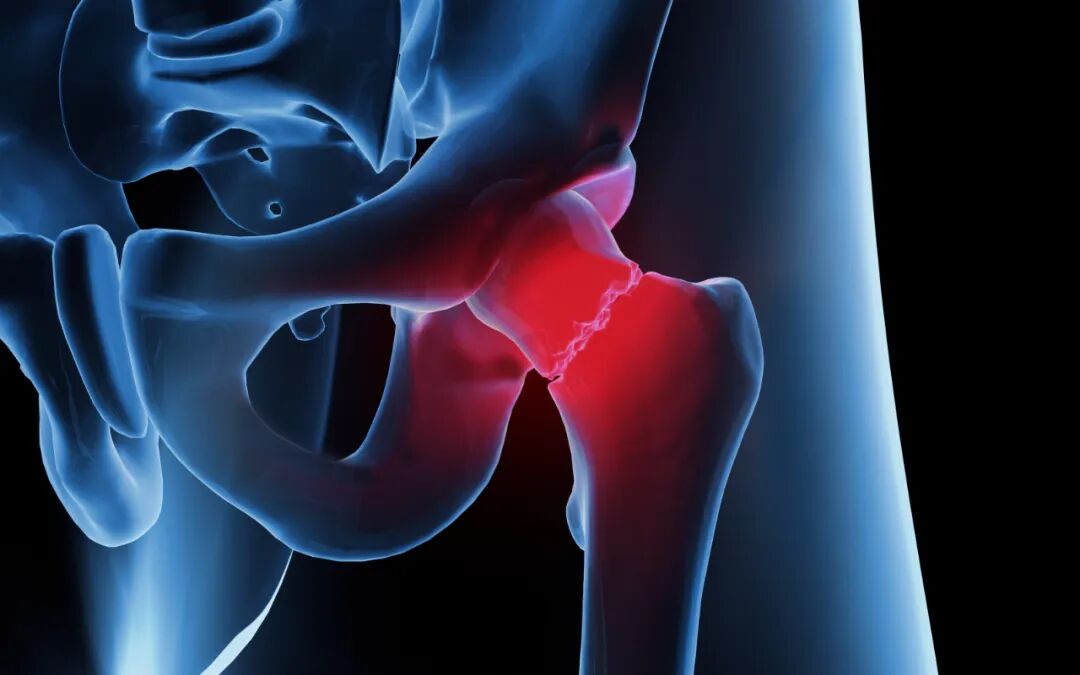

髋骨骨折主要是指髋臼骨折和股骨近端骨折,其中股骨颈骨折和股骨转子间的骨折属于最为常见的类型,约占老年人髋骨骨折的90%以上。对于老年人而言,髋骨骨折其实就意味着死亡,因为在保守治疗下,1年的生存率仅为50%。股骨颈骨折大部分是由突然跌倒或是外来暴力等原因引起的,骨折发生后,患者会出现髋部疼痛、不敢站立、患肢缩短等表现,但是也有一些在伤后仍能走路或骑自行车的情况,所以要仔细检查。

那么,要怎么判断髋骨骨折呢?

• 出现严重的臀部疼痛;

• 患者无法移动受伤的腿;

• 将重量放在腿上时会很痛;

• 受伤的腿向外旋;

• 出现腿长差异,受伤的腿比未受伤的腿短。